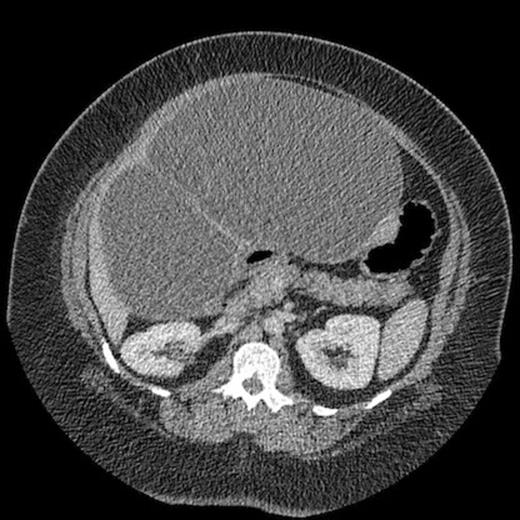

Laboratory evaluation was within normal limits except for mild hyperglycemia at 130 mg/dL, hyperbilirubinemia (total bilirubin = 1.7mg/dL, conjugated bilirubin = 1.02mg/dL), transaminitis (AST = 181 units/L, ALT = 423 units/L), and leukocytosis of 12,700 WBC/mm3. Carbohydrate antigen 19-9 and carcinoembryonic antigen were not measured. Dual phase CT imaging performed at our institution demonstrated a right hepatic multi-loculated cystic mass measuring 23 cm x 17 cm x 25 cm with internal septations and intrahepatic biliary dilation (Fig. 1).

Computed tomography demonstrating large intrahepatic septated cystic lesion